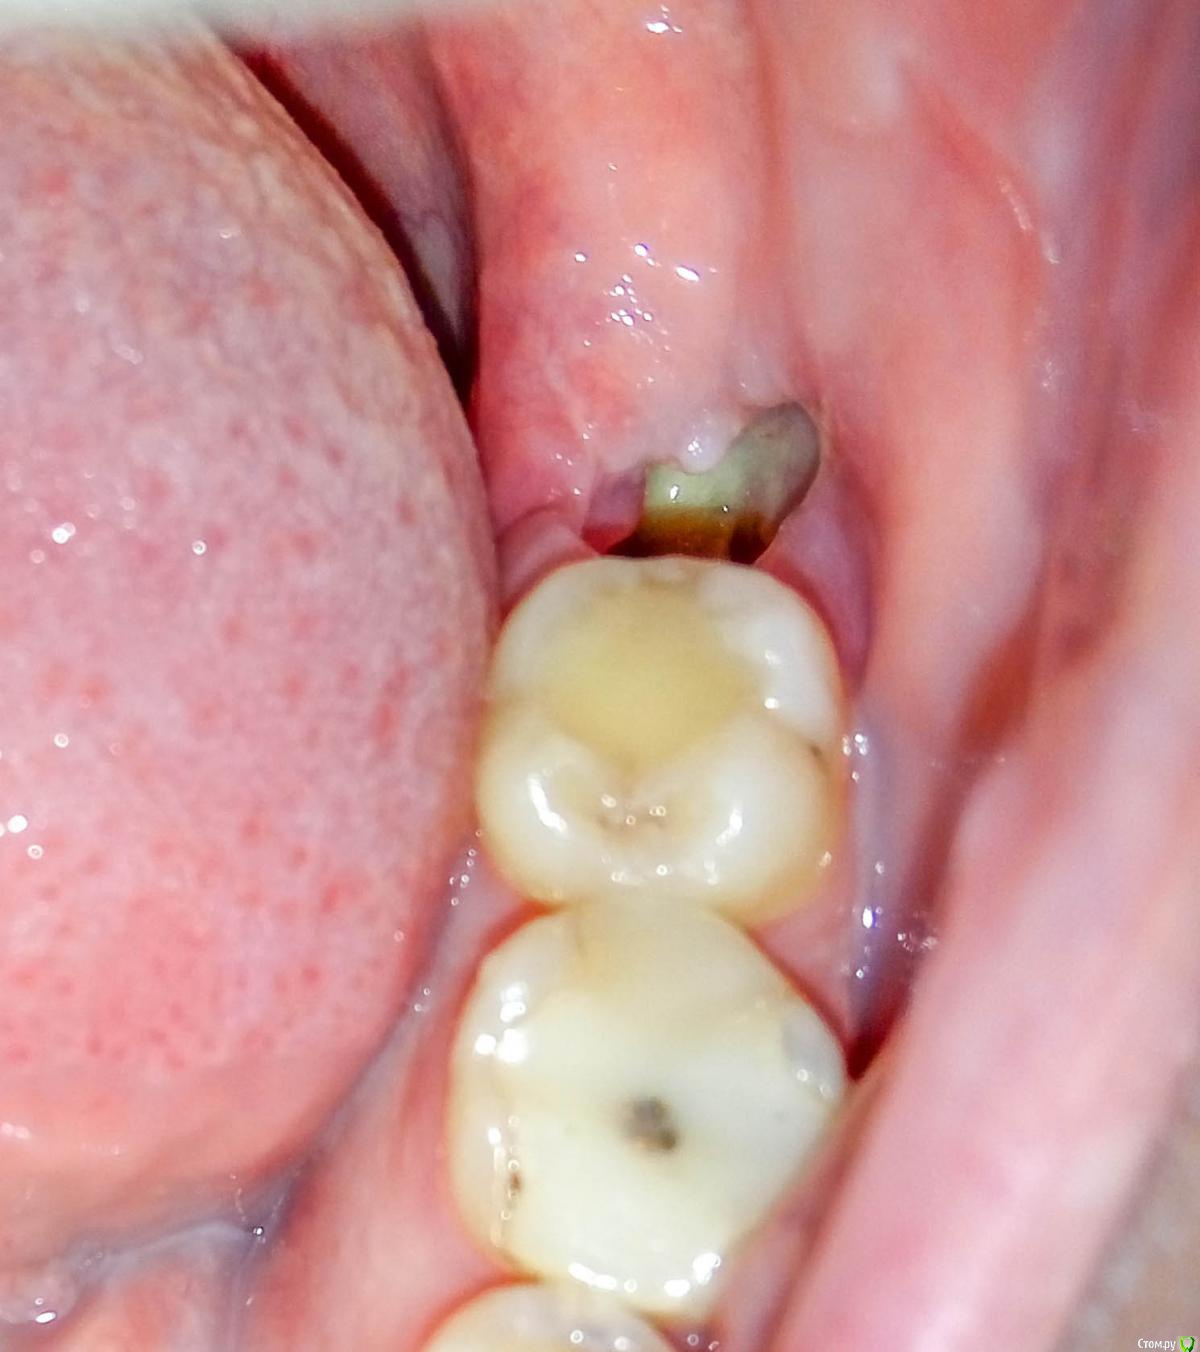

Ника9115 Опубликовано 1 марта, 2017 Поделиться Опубликовано 1 марта, 2017 (изменено) Здравствуйте, очень волнуюсь из за лунки, удаление было 14 февраля, сложное, более часа, лунка была заложена лекарством, сгустка не получилось, 2 недели ходила меняли губки + пытались 2 раза накладывать швы, один раз они сами рассосались на следующий день, а второй раз наложили которые надо снимать через неделю, так на след день они тоже разошлись, поэтому ложили постоянно губки, так как они выпадали постоянно, в то воскресенье положили последнюю и сказали больше не надо, всё так затянется, присутствую ноющие, иногда тянущие боли, не сильные, но не приятные, врач сказал, что лунка большая и болеть будет долго, вчера заметила внутри лунки какое-то уплотнение, со стороны языка, испугалась, пошла к врачу, он просто посмотрел , не трогал не чего, сказал всё нормально и отправил домой, сказал это лунка так стягивается, но что то мне подсказывает, что это не так, я все ровно переживаю... Живем в маленьком городе и больше обратиться некуда. Сказал если будут нестерпимые боли , то приходить. Фото прилагаю , первое и второе фото как вчера и сегодня , а последнее как было 22 февраля, прям как шишечка появилась. Изменено 1 марта, 2017 пользователем Ника9115 1 1 Ссылка на комментарий

Ника9115 Опубликовано 4 марта, 2017 Автор Поделиться Опубликовано 4 марта, 2017 Здравствуйте еще раз , удалили 14 февраля, то есть прошло почти 3 недели , десна немного ноет, и красная , при дотрагиваться языком немого больно, на фото выше видно лунку, там фибрин как я поняла, сегодня посмотрела в лунку, а там нету этого налета белого больше , шишечка та прошла помойму. Вот как выглядит лунка сейчас, боюсь воспаления опять , но вроде становится меньше, беспокоит десна, о что она красноватая и болит при дотрагивание. Ссылка на комментарий